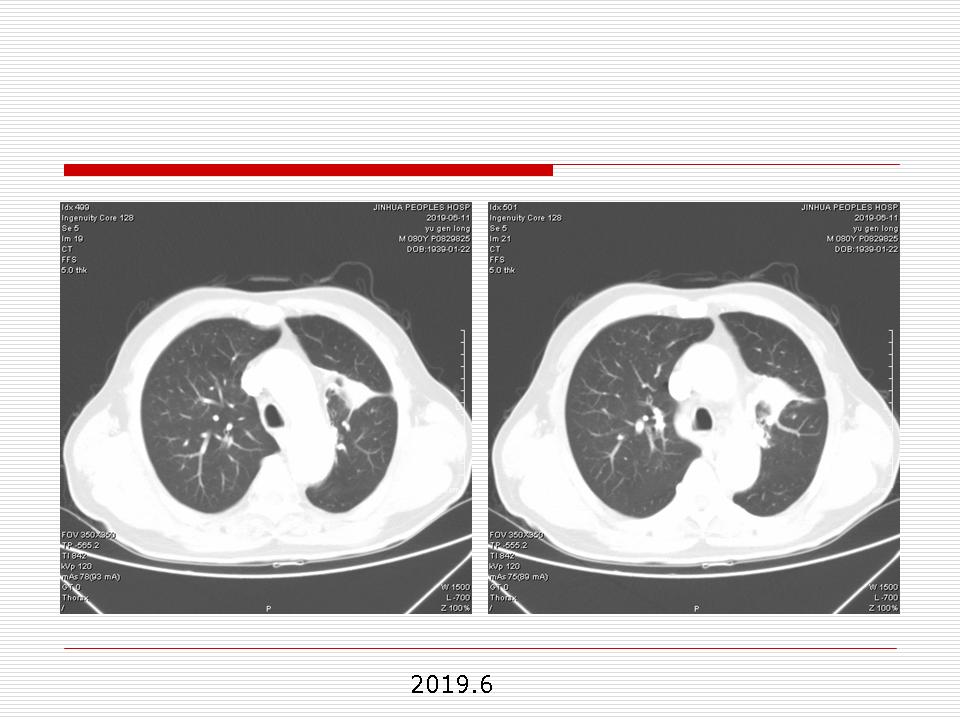

肺部阴影永恒且最重需要鉴别的是:到底是炎症还是肿瘤?但临床的病例中的影像表现难以界定或有些肿瘤特征,同时又有些炎症特点是非常常见的情况。作为临床医生我们怎么去总结分析,并找到之所以是炎症或之所以是肿瘤的细微差别或特点非常重要,也非常有用。2019.12.7浙江省2019年胸心外科学学术年会在宁波召开时,我的临床病例分析与经验总结<那些像肺癌的炎症与像炎症的肺癌>获得在大会交流的机会,以下为该PPT的内容,与你分享,希望对同道有益,有借鉴与启迪。若有探讨与进一不完善的建议,欢迎文末留言讨论: